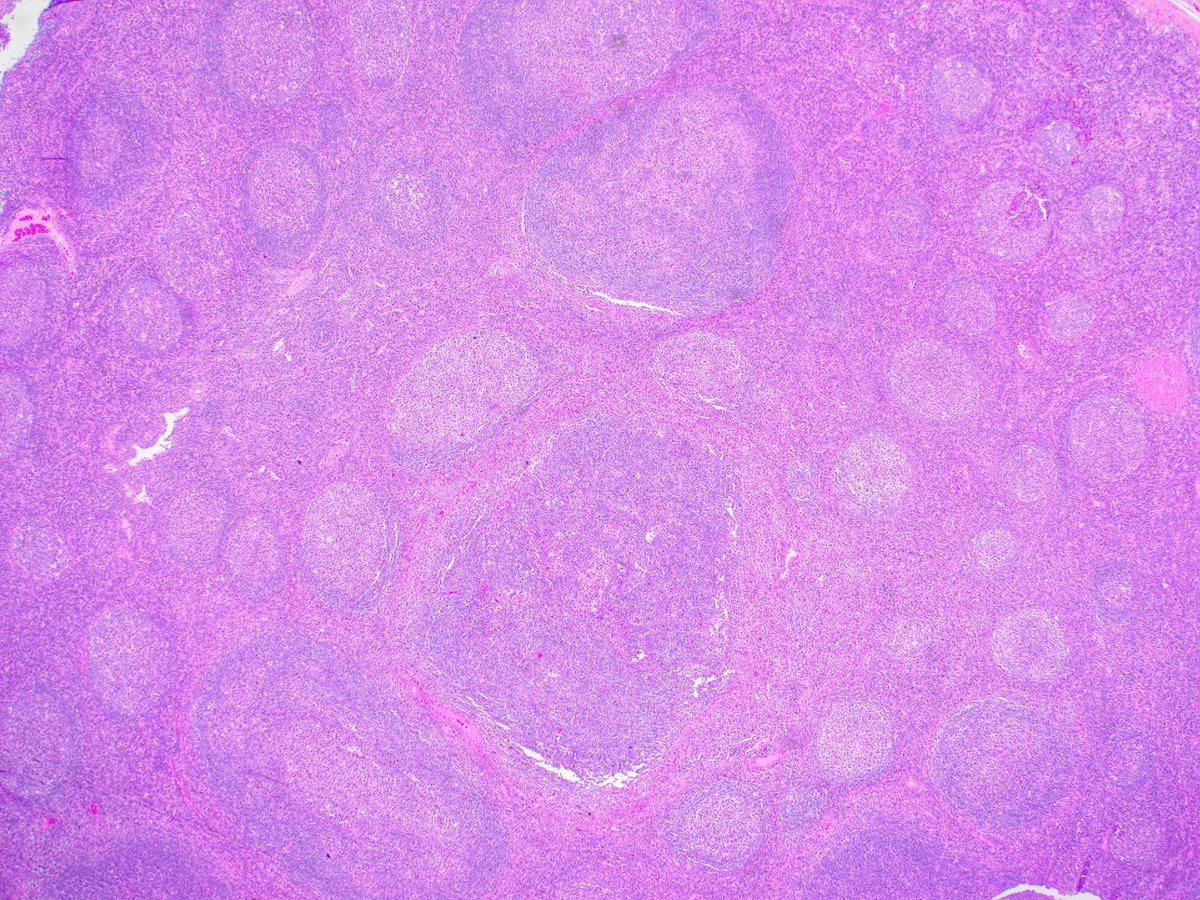

Yasamin Mirzabeigi, MD (@ymirzabeigi) 's Twitter Profile Photo

Let’s enjoy this cutie which pops up often on RISE and board exams, but not so frequently under the microscope! Once you see it, you’ll never forget it! A beautiful case of Sex Cord Tumor with Annular Tubules (SCTAT): • Positive for Calretinin, Inhibin, and WT-1 •

Let’s enjoy this cutie which pops up often on RISE and board exams, but not so frequently under the microscope! Once you see it, you’ll never forget it!

A beautiful case of Sex Cord Tumor with Annular Tubules (SCTAT):

• Positive for Calretinin, Inhibin, and WT-1